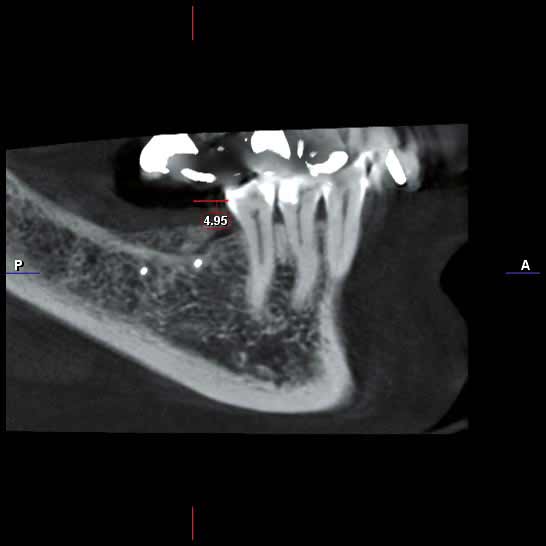

Three implants placed in a narrow posterior mandible